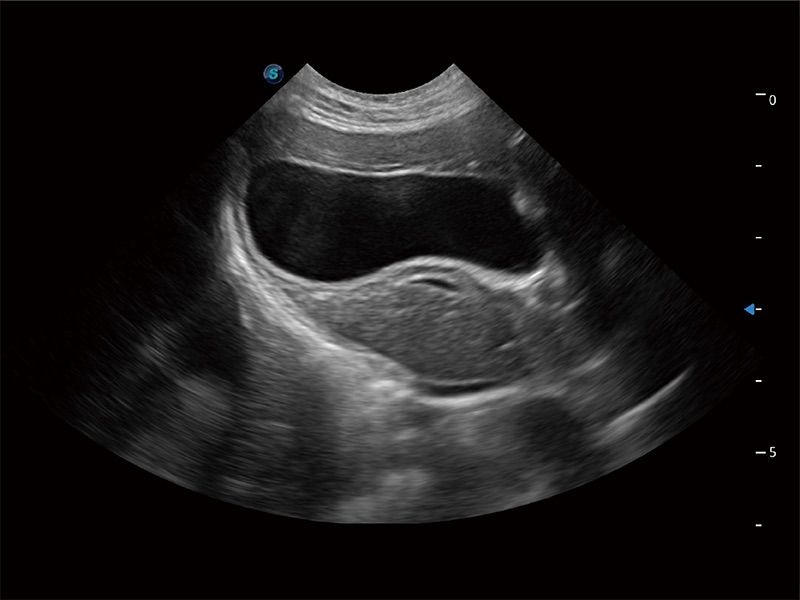

ProPet 80 配备了丰富的心脏探头群、先进的成像技术和专业的心脏测量工具,可帮助动物医生为不同体型和生理结构的动物提供心脏和心肌功能的全面评估。

ProPet 80 专为动物医生设计,对不同的动物体型和生理结构作出了针对性的优化。通过动物影像专用软件,可满足个性化的应用需求,帮助动物医生获得更精确的诊断数据。

为精细结构及组织边缘提供高清晰度的图像和更大的成像视野。帮助减轻医生的用眼疲劳,快速精准获得测量的数据。